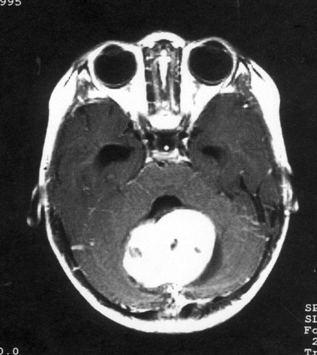

问题 病历摘要:??患儿男性,11岁。半年前开始出现行走不稳,常无故跌倒。半月前出现发作性剧烈头痛,伴恶心呕吐。体检:T36℃,P100次/分,R22次/分,BP100/60mmHg,神清,言语较缓慢,双眼外展约不及边,双眼侧视时有小幅度水平眼震。四肢肌力正常,右上肢肌张力较低,坐位姿势不稳,常不自主摇晃,双上肢指鼻不准,行走蹒跚步态,足距扩大,身前倾。 下一步应首先采取哪些措施?提示:多次缝合伤口,仍有脑脊液渗漏。